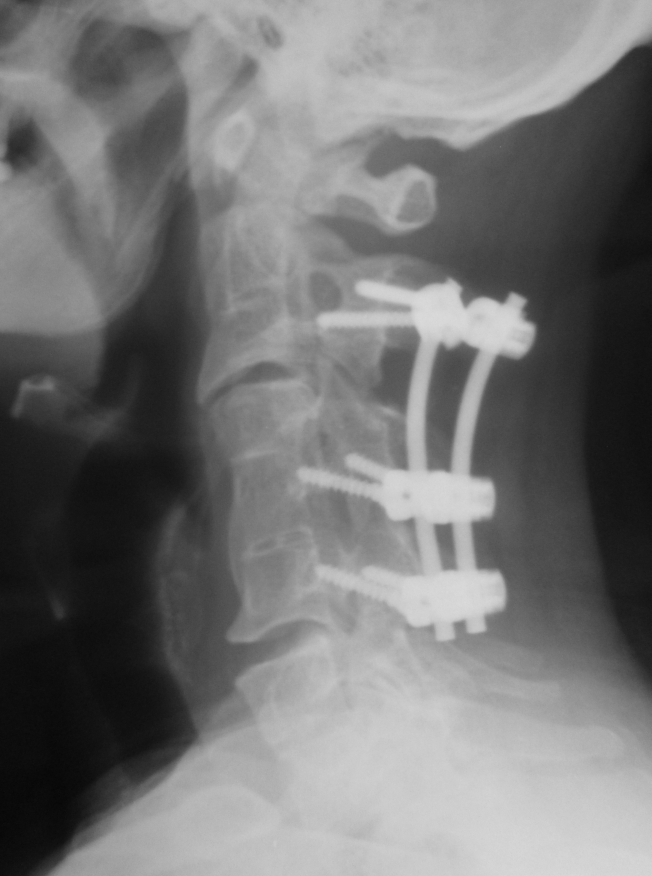

Klippel-Feil PostOp AP Grafisi Klippel-Feil PostOp Lateral Grafi Klippel-Feil Postop BT C2 Seviyesi

Resim 3: Postop direkt grafilerde C2-C6 seviyesindeki stabilizasyon sistemi görülmektedir. C2 seviyesinde intralaminar (en sağdaki resim), C5-C6 seviyelerinde lateral kitle vidaları kullanılmıştır.